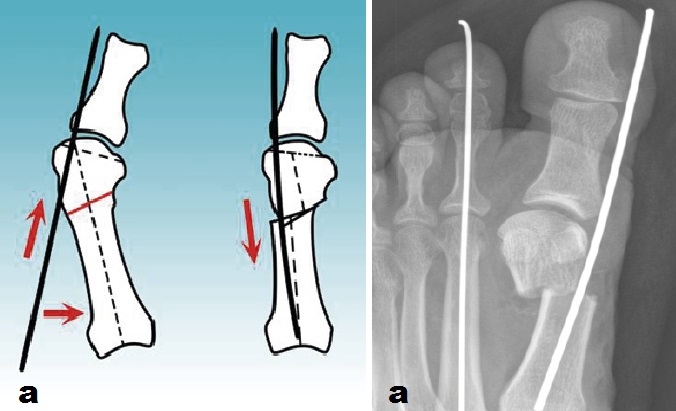

Le deformità dell’avampiede coinvolgenti le dita, sono state tipizzate allo scopo di stabilire la tecnica chirurgia più adeguata: dalla correzione dell’alluce valgo isolato con tecnica mini invasiva SERI (a) ideata dal Prof. Giannini, fino alla correzione di complesse deformità coinvolgenti i metatarsali esterni e tutte le dita. Per ogni tipo di intervento, a seconda dell’estensione della correzione sono stati organizzati percorsi di trattamento diversi.

Caso 4: Alluce valgo e dito ad artiglio

Femmina di 63 anni affetta da alluce valgo e deformità ad artiglio del 2° dito associata a lussazione della 2° metatarsofalangea (a). La deformità dell'avampiede era causa di metatarsalgia resistente al trattamento medico e ortesico. Sottoposta ad intervento chirurgico di osteotomia correttiva del primo metatarso con tecnica S.E.R.I., riduzione della lussazione metatarsofalangea e correzione della deformità ad artiglio del 2° dito (b), a distanza di 8 mesi dall'intervento chirurgico, l'avampiede si presenta corretto e la metatarsalgia risolta. Il controllo radiografico (c) mostra il rimodellamento del metatarso conseguente all'osteotomia.